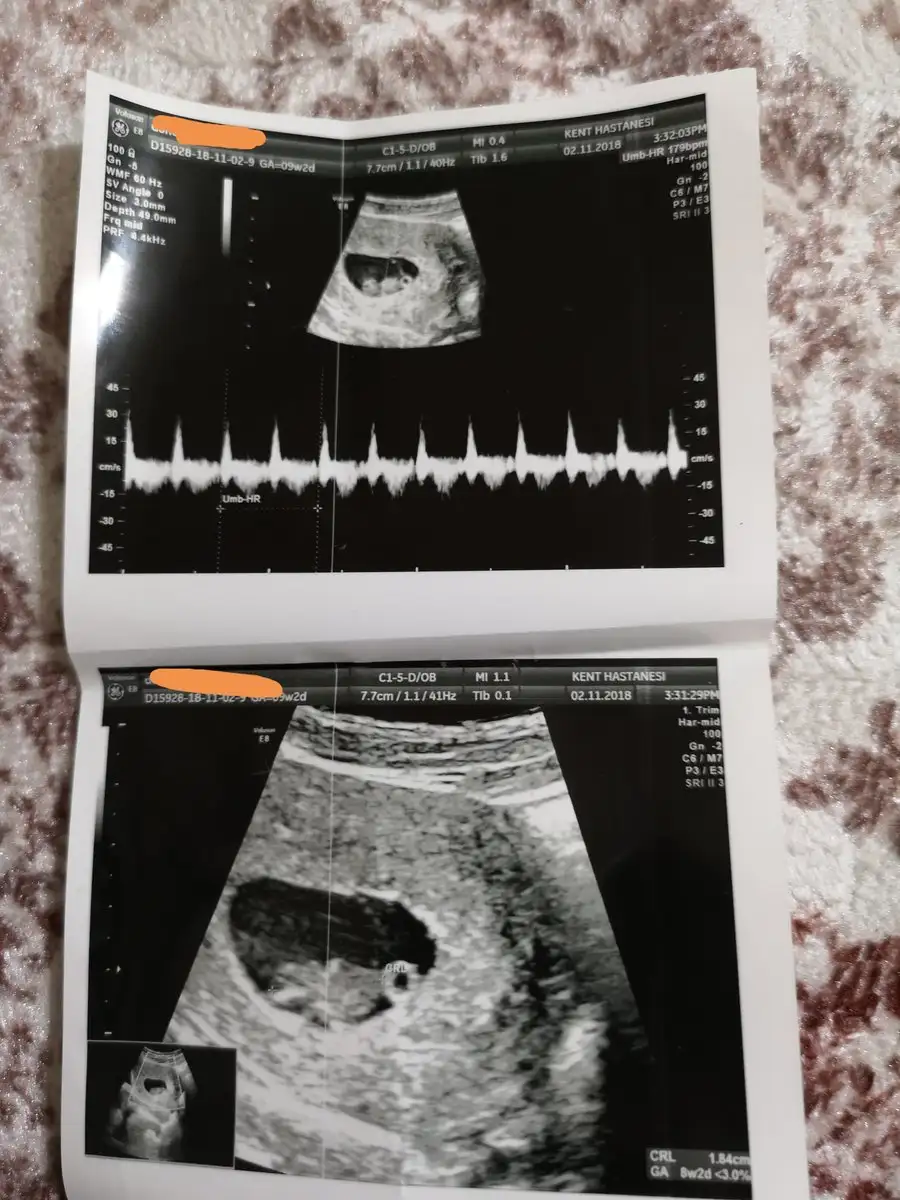

Benimde bugün kontrolüm vardı biraz önce çıktım çok şükür büyümüş minnoş1.6 cm olmuşuz kolları bacakları kafası artık çok net seçiliyor çok çok şükürler olsun

Aynen kuzum çıktınmı sen doktordan? Ultrason fotosu varsa sende at :)Benim bebegim 3.3 cm olmuş 1 gün bile nasıl fark ettiriyor gerçekten :) insan bi tuhaf oluyo o insana benzemeye başladıkça dimi :)

Ben de doktora gittim bugün. Daha büyük sanıyorduk sat ' a göre fakat henüz 5 hafta 4 günlükmüş. Henüz küçükmüşüz ama Yine de buyrun kesemiz, yolk sac'ımız ve hemen sağında keseye bitişik olan pek anlaşılmayan bir yapıdaki halimiz.kalp atışımızı da gördük elhamdülillah. Darısı gün bekleyenlerin başına... Eki Görüntüle 2202575